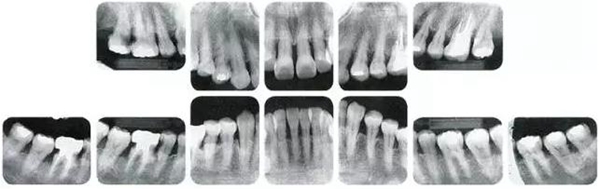

●參考病例① 35歲女性

35歲女性。妊娠4個月。過去雖然接受過刷牙指導,但菌斑控制狀態(tài)依然不理想?;颊哂邪l(fā)現(xiàn)自己刷牙時牙齦出血。

牙周病的發(fā)展因部位不同而發(fā)展程度不同的。10點后的狀態(tài)參考病例①和參考病例②的磨牙處的狀態(tài)相比較,思考下沒接受治療病情發(fā)展的特別性吧。

參考病例① 35歲女性

在左下第一磨牙在25歲時近中處可以看到垂直性的骨吸收,但35歲時吸收停止,原本沒有見到的遠中處骨吸收的,現(xiàn)在卻吸收得很嚴重。

在右下處,原本有大量骨吸收的第一磨牙處的吸收卻變緩慢,原本沒有吸收的第二前磨牙卻出現(xiàn)了吸收。出現(xiàn)吸收的左上第一磨牙的遠中處,吸收得越來越多了。

把10年間的變化做成表格。牙周病的發(fā)展根據(jù)各個人會不同,即使通一個人,不同牙齒,不同牙面發(fā)展的狀態(tài)也不同。